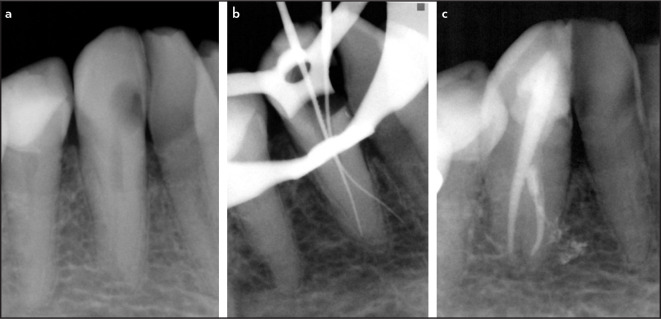

This is a series of 7 cases in which the operator penetrated lateral canals with instruments. Two teeth presented with irreversible pulpitis, 4 with necrotic pulps, and 1 with previous treatment. Except for the teeth with pulpitis, all the others were associated with apical periodontitis. The main root canal was always relatively straight, with the lateral canals at the middle third of the root. Suggestive images of lateral canal presence were seen on periapical radiographs in five cases. The clinician introduced intentionally small hand instruments in the lateral canal in 5 cases, while the penetration was fortuitous in the others. The lateral canals were obturated in all cases. Follow-up examination was possible in five cases, all of them showed evidence of successful clinical and radiographic outcomes. Introducing files into lateral canals may permit some preparation and penetration of irrigant solution, favoring disinfection and, consequently, enhancing the treatment outcome. (EEJ-2023-05-063).

Abstract Image